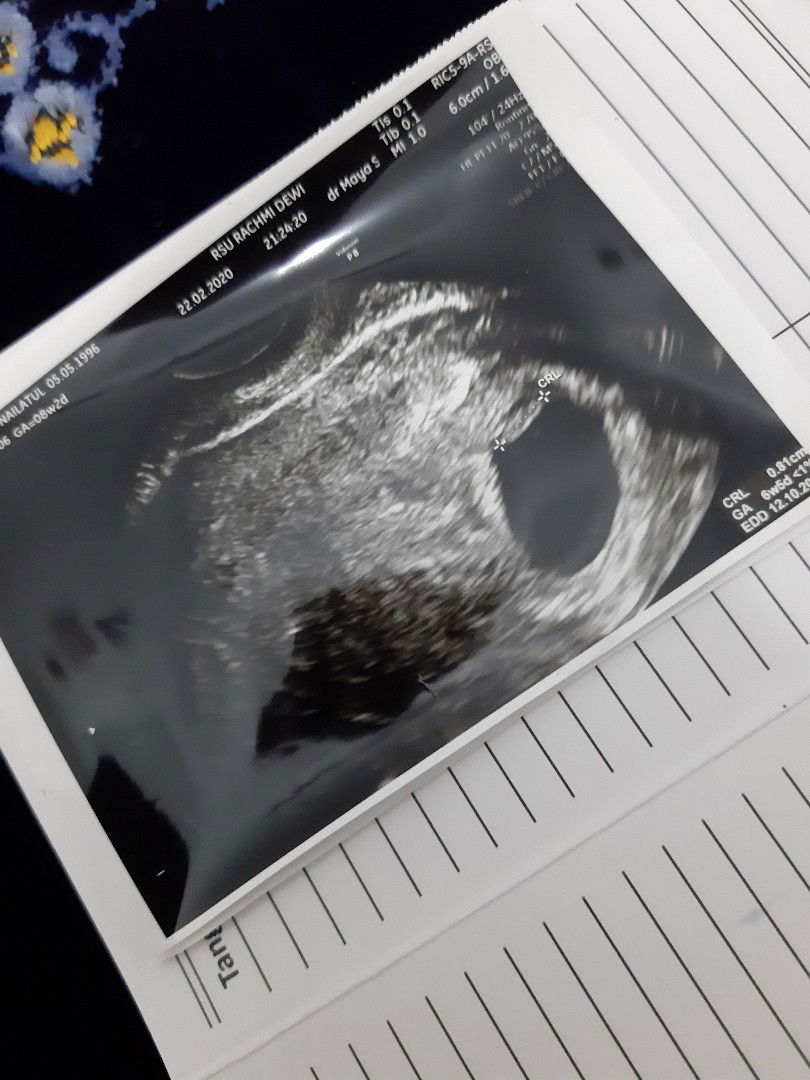

26 September 2020, aku melahirkan putra pertama kami dengan proses SC karena KPD dan CPD, setelah SCpun aku masih bisa nenenin adek langsung.. karena produksi ASI alhamdulillah lancar, aku bingung mau KB apa? karena takut mengganggu perjalanan mengASIhi. saat itu nifasku 36 hari kemudian berhenti 10 hari, tb2 dtg lagi sampai hari ke 60. setelah pertimbangan panjang, kami baru berencana memasang KB IUD, tp kata obgynnya nunggu mens lagi.. eh mens yang ditunggu tunggu tak kunjung datang. akupun tak curiga sedikitpun. karena ada yg bilang bahwa mengASIhi juga bs jd kb alami. desember akhir, tiba2 hasil pompa menurun. bisanya sekali pompa 330ml, tb2 menjadi 270ml.. kufikir mungkin karena setres dan kecapekan, akhirnya saat liburan akhir tahun ku coba pijat laktasi (ternyata saat itu sudah hamil tp kami belum tau) setelah pijat laktasi, produksi asipun masih sama(tidak ada peningkatan). akhirnya mencoba ASI booster macem2, mulai dari jamu(setiap hari jamu parem), pil, teh, susu, madu dll..tp tak ada hasil. semakin hari hasil pumping semakin berkurang hingga pada titik terendah, sekali pumping 30ml (saat bulan februari). pada awal februari, tanpa gejala, tanpa kecurigaan, tiba2 aku menangisi nasi bungkusan lauk ikan jaer ketika nasi itu dimakan suami. dan aku nangis layaknya anak kecil. mintak belikan soto, tp ketika dibelikan g dimakan. akhirnya suami curiga dan nyuruh tespek. masyaallah 😭 garis 2.... padahal tesnya malam hari. masih kurang legah, akhirnya pagi haripun tes lagi, dan hasilnya tetep garis 2. semenjak itu, kuberhentikan untuk minum jamu parem. kehamilan ke2 yang benar2 tdk diduga2. kukabari suami, dan kami berdua menangis. suami takut dg kondisiku karena baru SC beberapa waktu yg lalu.. suami juga kasian anak pertama kami yang saat itu masih 5 bulan 😭. bergegaslah kami ke obgyn yang menangani SC saat anak pertama. saat diusg, ternyata dekbay sudah berusia 3 bulan 😭detak jantungnya sudah terdengar, sedangkan anak pertama kami masih 5 bulan. akhirnya kami memutuskan untuk menyembunyikan kehamilan ke2 dari org tua, mertua, kluarga dan sekeliling. demi kelancaran memberi ASI ekslusif ke kakak. karena kami tinggal di desa, menyusui saat hamil tidak diperbolehkan, sedangkan dokternya memperbolehkan, asal tdk terjadi kontraksi.. sudah konsultasi dg konselor laktasi juga diperbolehkan, tp ternyata susu pada ibu hamil renda karbohidrat dan glukosa tp dy tinggi imun dan protein.. tp kami tetap memberikannya, sampai tiba masa MPASI 6 bulan. mulailah aku rajin masak tiap menu kutambah kurma sbagai pengganti glukosa yg sedang menurun di ASI. sungguh perjuangan sekali... mempertahankan BB kakak dg kondisi aku sedang hamil. sekitar 2 bulan kami menyembunyikan kehamilan dari sekitar. mulailah kami membuka mulut dan mengabari keluarga bahwa si kakak mw punya adek. saat itu usia kakak 7 bulan dan aku hamil 5 bulan.. benar dugaan diawal, ortu tidak mengizinkan aku mengASIhi sikakak, dg sedikit drama, kakak full sufor mulai usia 8,5 bulan.. dan skrg kaka usia 9,5 bulan. awal2 rekan kerja, saudara ngejulidin kehamilan ke2.. yang bilang "kasian kakaknya nanti g keurusloh, lho kakaknya kok skrg kurus? wah karena sundulan ini" down? banget.. aku semakin teropsesi menaikkan BB kakak. sampai aku lupa anakku adalah manusia, dy tdk mau makan dg paksaan.. akhirnya aku sadar dan mulai tdk menghiraukan kata org. yg penting anakku sehat, perkembangannya sesuai. alhamdulillah kehamilan ke2 ini tanpa mual muntah, jahitan aman, ngidam tetap ada, kmn2 sepedaan sendiri.. cuman keluhan dikehamilan ke2 ini ada pada MENTAL 😭 mental karena omongan sekitar.. untuk persalinan ke2, insya allah SC lagi. dan langsung pasang IUD. mohon doanya ya moms, hpl akhir agustus 2021... semoga teman temanku yang sedang memperjuangkan 2 garis, segara Allah ijabahi... semangat... #sundulan #hamilpascasc2bulan #kbiud #scke2 #sesar #jangandibully #CeritaKehamilanTAP